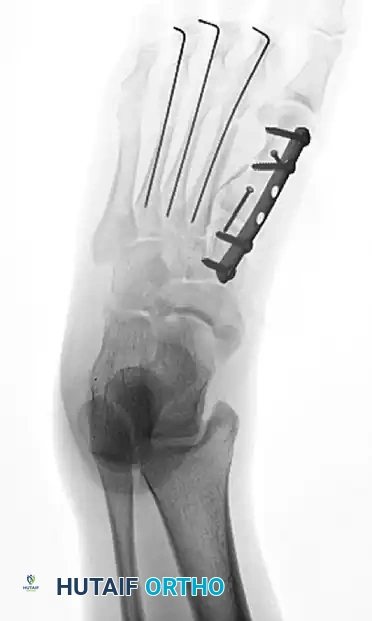

- First Ray Stabilization: The first metatarsal is the primary weight-bearing axis of the forefoot. It must be anatomically reduced and rigidly fixed. Open reduction and internal fixation (ORIF) using a low-profile titanium plate and screws is the gold standard.

- Lesser Ray Stabilization: Once the first ray is restored to its anatomic length and rotation, the lesser metatarsals are addressed. Because of the comminution and the need to minimize soft tissue stripping in crush injuries, closed reduction and percutaneous pinning (CRPP) with stout Steinmann pins or K-wires is often preferred over formal plating for the lesser rays.

Postoperative anteroposterior radiograph showing anatomic restoration of the forefoot. The first metatarsal has been rigidly stabilized with plate and screw fixation, while the lesser metatarsals have been aligned using percutaneous Steinmann pins.